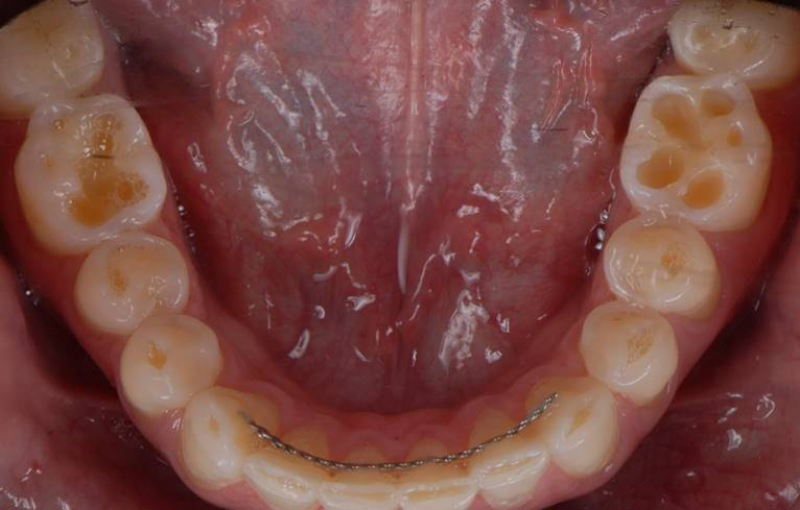

Self-induced vomiting increases the risk of dental erosion by a factor of 5.5 compared to healthy controls. These intrinsic erosion lesions are most commonly found on the palatal surfaces of the maxillary teeth, followed by the occlusal and then the buccal surfaces (Figs. 1–5).